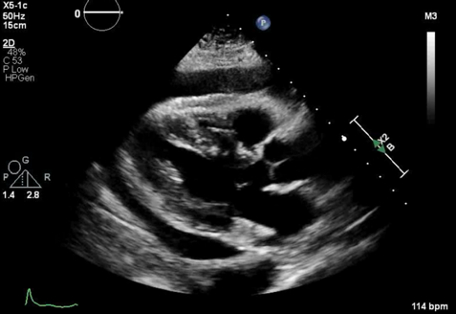

A 62-year-old female presented to the emergency room with a one-day history of non-radiating, achy chest pain worse with lying down. She was febrile at 38.4 °C and mildly tachycardic. ECG showed diffuse ST-elevation (Figure 1). Laboratory values were significant for WBC 13.6 k/μL, ESR 106 mm/hr, and CRP 30.48 mg/dL. Chest CT revealed new trace pericardial fluid or thickening possibly from trace pericardial fluid or pericarditis. Blood cultures grew H influenzae and she was started on IV ceftriaxone. She became hypotensive and echocardiogram showed normal left ventricular systolic function and a moderate-sized, circumferential pericardial effusion with compression of right ventricle consistent with tamponade (Figure 2). She underwent emergent pericardiocentesis which drained 260 mL of purulent fluid (Figure 3). Pericardial fluid studies showed WBC of 107.5 k/μL with 100% neutrophils. Pericardial fluid culture remained negative. Following initial drain removal, her hospital stay was complicated by cardiac arrest, recurrent pericardial effusions requiring repeat drain placement and a pericardial window, which resulted in a right ventricle laceration. She slowly recovered and was discharged home with a four-week course of levofloxacin.